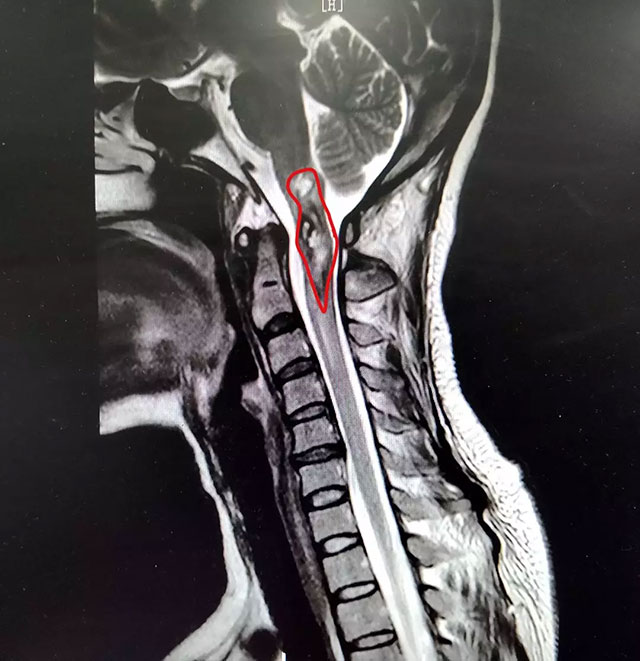

脊髓出了問(wèn)題,人們往往會(huì)聯(lián)想到癱瘓和死亡。脊髓腫瘤,尤其是位于延髓-頸2(第二節(jié)頸椎)這個(gè)“雷區(qū)”位置的腫瘤,由于周圍密布重要的神經(jīng)和血管,手術(shù)風(fēng)險(xiǎn)極高。

▲ 潘仁龍主任指出患者病灶位置

在患者身體條件允許的情況下,通過(guò)對(duì)患者進(jìn)行選擇性脊髓血管造影檢查,明確診斷其延髓-頸2位置的占位病變?yōu)楹>d狀血管瘤伴脊髓空洞癥。

潘仁龍主任介紹,延髓的主要機(jī)能是調(diào)節(jié)內(nèi)臟活動(dòng),許多維持生命所必要的基本中樞(如呼吸、循環(huán)、消化等)都集中在延髓,有“生命中樞”之稱。這個(gè)部位一旦受到損傷,常會(huì)迅速引起死亡。

而位于脊髓高段的頸髓共有7節(jié)段,出現(xiàn)腫瘤和空洞時(shí)會(huì)引起運(yùn)動(dòng)和感覺(jué)障礙,嚴(yán)重時(shí)也是致命的。

▲ 經(jīng)過(guò)治療,患者脊髓內(nèi)出血得到控制

姜女士患上的海綿狀血管瘤,是隱匿性脊髓血管畸形的一種。雖然普遍認(rèn)為這是一種良性腫瘤,但由其并發(fā)髓內(nèi)出血時(shí),會(huì)導(dǎo)致神經(jīng)功能障礙。潘仁龍主任表示,由于這一部位的手術(shù)難度較大、風(fēng)險(xiǎn)很高,結(jié)合患者實(shí)際狀況和本人意愿,決定對(duì)其采取對(duì)癥保守治療方案,以期讓患者減輕癥狀,盡可能恢復(fù)活動(dòng)能力。